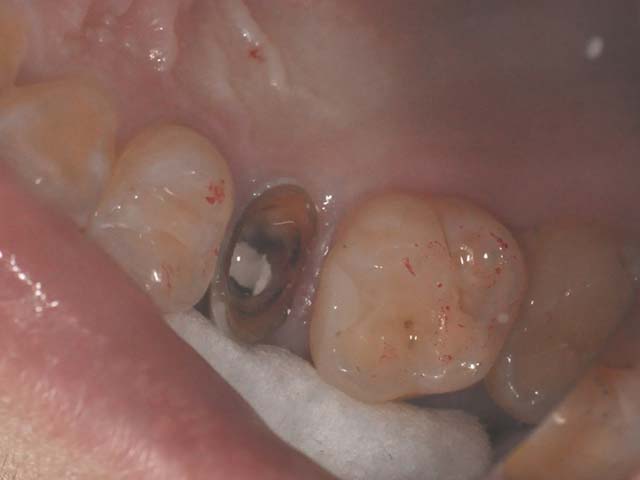

齒槽骨保存術+植牙 首頁 案例分享 人工植牙 齒槽骨保存術+植牙 STEP1拔除掉無法使用的斷裂牙根 STEP2齒槽骨保存術—使用骨粉填補拔牙傷口 術前 V.S 術後 植牙第一階段—植入牙根 植牙第二階段—製作正式假牙